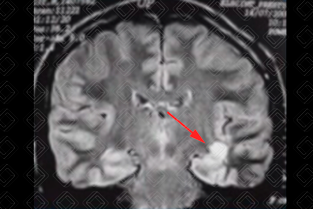

Descrição das imagens: Ressonância magnética de crânio, sequência FLAIR, evidenciando na primeira imagem lesões hiperintensas nos lobos temporais (seta vermelha). Na segunda imagem observamos os clássicos dedos de Dawson, lesões hiperintensas, perpendiculares aos ventrículos laterais (setas amarelas).

• Tipicamente envolvem corpo caloso, fibras em U, tronco cerebral, lobos temporais, cerebelo e região medular;